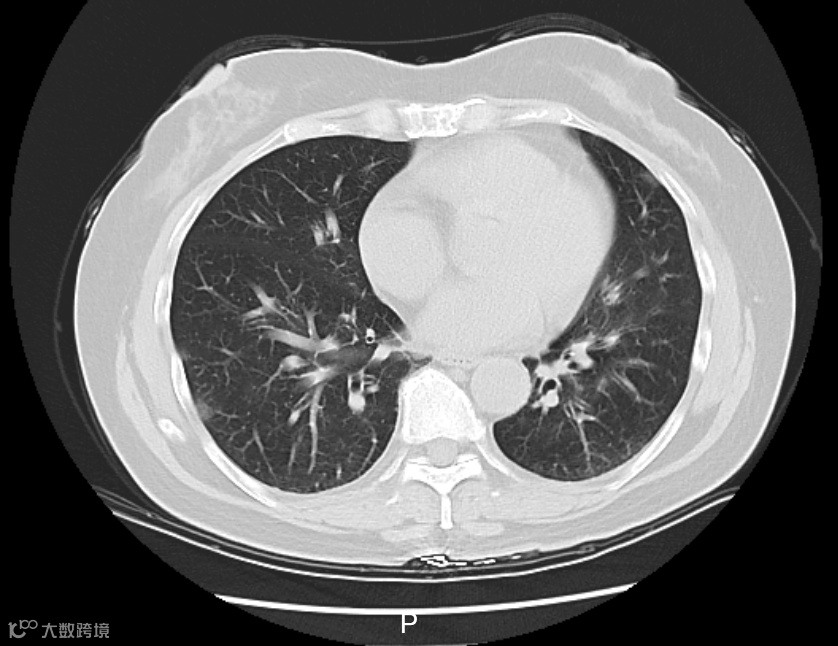

据悉,李阿姨在当地接受了一些治疗,但体温仍居高不下。家中同行的6个人,有5个人都先后发烧了。医生判断,李阿姨大概率是得了传染性较强的呼吸道疾病,立即给她安排了血常规、相关病毒抗原检测,以及更清晰的肺部CT检查。

△李阿姨肺部CT影像

检测结果显示,李阿姨得了病毒性肺炎,甲型流感病毒核酸呈阳性。